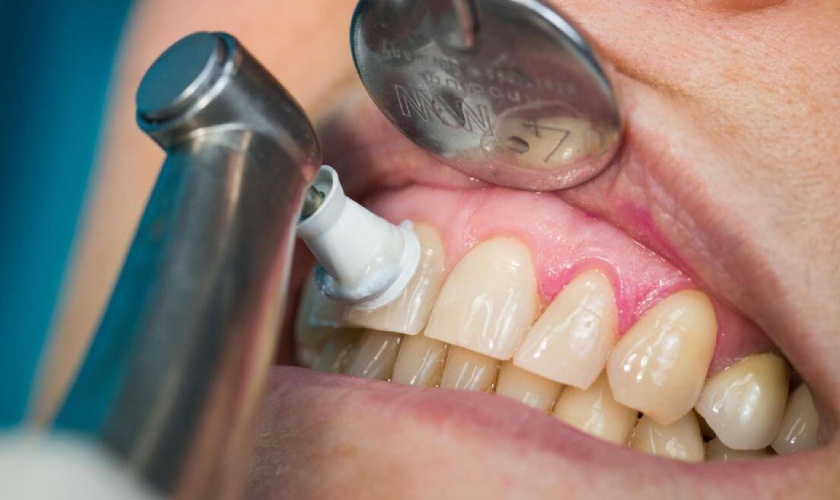

Trước đây, để cạo vôi răng thì bác sĩ thường sử dụng các dụng cụ thủ công, tác động nhiều đến men răng, đồng thời có thể gây đau, chảy máu và ảnh hưởng đến sức khỏe răng miệng. Hiện nay, các nha khoa hiện đại thường áp dụng công nghệ cạo vôi răng bằng sóng siêu âm, giúp lấy vôi răng một cách nhanh chóng, nhẹ nhàng, không đau.

Vì thế, chi phí cạo vôi răng hiện đại có thể cao hơn với cạo vôi răng truyền thống, tuy nhiên kết quả mà bạn nhận được hoàn toàn xứng đáng.

Nơi đây không chỉ quy tụ đội ngũ bác sĩ nha khoa giỏi, giàu kinh nghiệm mà còn ứng dụng công nghệ hiện đại nhất hiện nay trong việc cạo vôi răng, đó là máy cạo vôi răng siêu âm, đặc biệt quy trình thực hiện theo tiêu chuẩn Y khoa quốc tế, tuân thủ nghiêm ngặt yếu tố vô trùng, cùng với đó là dịch vụ chăm sóc khách hàng chu đáo, tận tình.